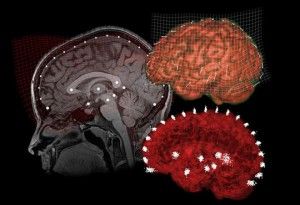

Mapa cerebral del placer de la mujer

Hoy hemos podido leer en varios medios de comunicación la publicación de la noticia que encabeza la presente entrada. El hallazgo, o mejor dicho, este logro se ha llevado a cabo gracias al doctor en psicología Barry R. Komisaruk. El artículo fue publicado en la revista ‘Journal of Sexual Medicine’ en Julio de este año. A los […]